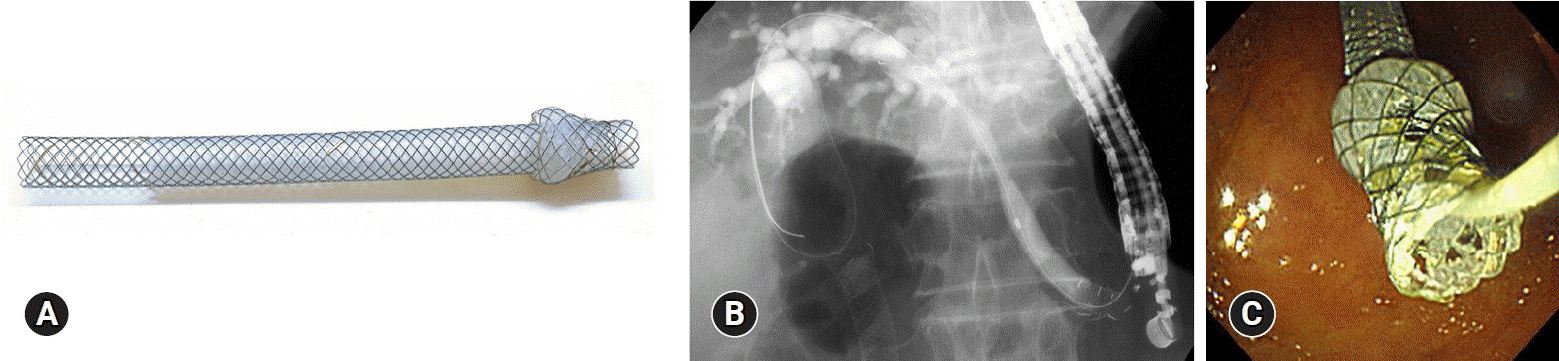

ARMSs were developed to prevent RBO and reflux cholangitis caused by the reflux of intestinal contents and food impaction, which are among the causes of RBO after stent placement. Although various shapes of antireflux valves have been reported, mainly from Asia, two types of ARMSs are available: the chimney and duckbill types.21,22 Currently, there is no clear evidence that ARMSs prolong the TRBO. However, in patients in whom the cause of the initial stent occlusion is reflux cholangitis or in patients prone to reflux cholangitis, such as those with duodenal stenosis, ARMSs can be useful22 (Fig. 1) and should be considered an option.

Fig. 1.

A case of repeated reflux cholangitis after fully covered self-expandable metal stent placement and duodenal stenting for distal biliary obstruction and duodenal obstruction. (A) Duckbill biliary stent (Kawasumi Laboratories Inc.): The stent has two additional meshes at the distal end to regulate the opening of the valve; the valve is normally closed to prevent reflux of duodenal contents into the bile duct, but opens to allow bile to flow out when the bile duct pressure increases. (B) Radiographic image: Duodenography showing reflux of the contrast medium into the bile duct. (C) Radiographic image: After placement of the Duckbill biliary stent, duodenography shows no reflux of the contrast medium into the bile duct.